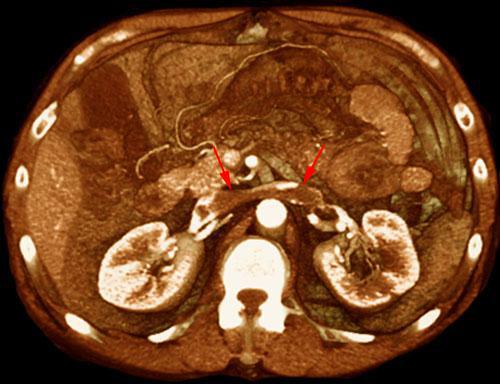

Trombosis de la vena renal izquierda